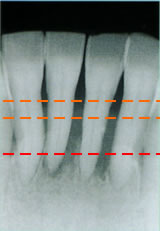

骨(歯槽骨)の状態

- 正常

歯槽骨が正常な位置にあります。

- 中度の歯周炎

歯槽骨の位置が下がってきています。

- 重度の歯周炎

歯槽骨の位置がかなり下がり、

歯の大部分が見えている状態です。